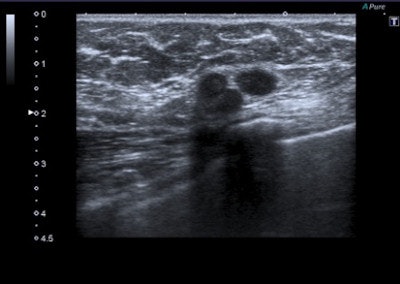

A 45-year-old woman with a palpable mass in the lower-outer quadrant 2 cm away from the nipple. There was no erythema, ecchymosis, skin ulceration, or dimpling and no axillary lymphadenopathy was detected. Baseline ultrasound shows an isoechoic lump with regular margins, with some cystic areas within. At elastography the nodule presents a color map score 4 according to the Ueno-Itoh classification, with absence of elasticity, depicted as a completely blue area with a different peripheral glow. Placing two different regions of interest (in normal breast tissue and within the nodule), strain ratio obtained is 8.96. Gross pathology confirmed a cystic cancer.

Malignant lesions usually present with features such as acoustic shadow, spicules, indented margins, hyperechogenic halo with desmoplastic reaction around the lesion, calcifications, spreading along the ducts, and significant vascularization. Cancer can also have nonspecific features such as uneven architecture and gland edema.

Tumor stiffness is a characteristic of extracellular matrix, modulated by collagen cross-linking. Malignant lesions are less prone to deformation by pressure than normal breast tissue and have a more complex elastic modulus. Softer malignant lesions, including medullary, mucinous, papillary, cystic, and some necrotic infiltrating ductal carcinomas, are uncommon.

Elastography is often used in "uncertain" lesions classified as BI-RADS 3 and 4, but it does not change medical protocol in cases of BI-RADS 1, 2, and 5 lesions. The mean elasticity score of color map was significantly higher for malignant lesions than for benign lesions (p < 0.001), usually mainly represented as blue areas in the color map.